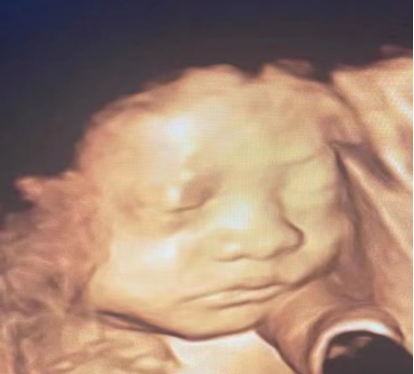

胎儿系统产前超声检查(俗称“大排畸”),是整个孕期最重要的超声检查之一!

超声医生会通过超声仪器检查胎儿的生长发育、胎盘、羊水情况以及胎儿各个器官和系统的发育情况,尽可能观察并显示胎儿主要解剖结构,排除大部分、严重的畸形。